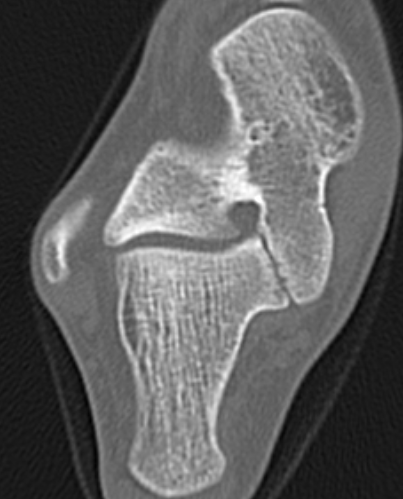

CT

TC coalition middle facet

Complete synostosis of the medial TC joint with OA of the posterior subtalar joint